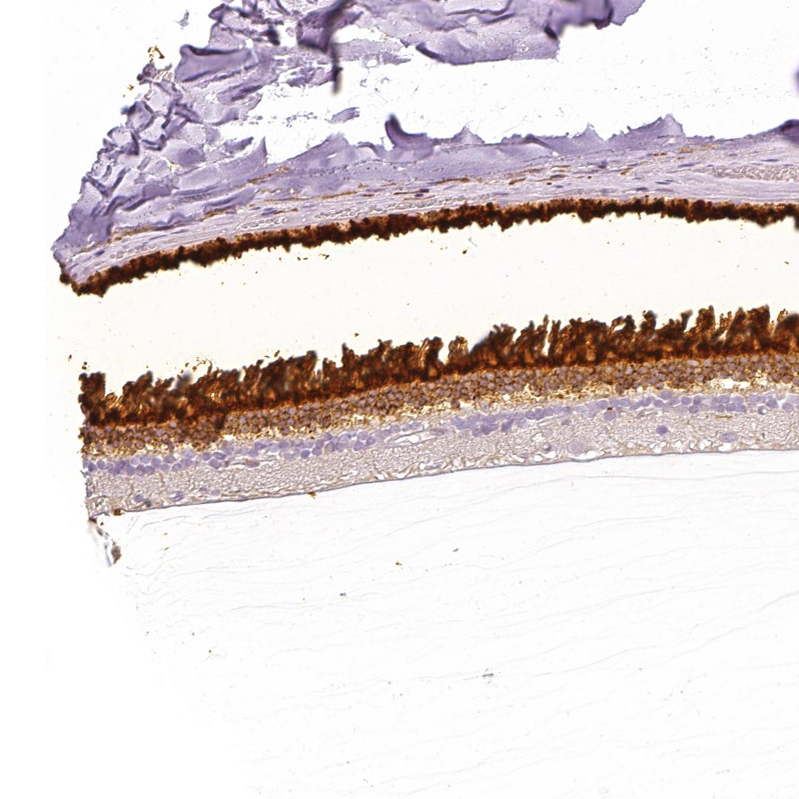

Immunohistochemical staining of human cerebral cortex, eye, retina, liver and skeletal muscle using Anti-IMPG1 antibody HPA030332 (A) shows similar protein distribution across tissues to independent antibody HPA027142 (B).